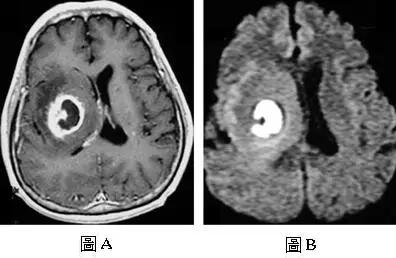

50 歲男性患者,主訴左側肢體無力已經二個星期,接受磁振造影檢查,圖 A是注射顯影劑後的 T1 加權影像,圖B是擴散加權影像( diffusion-weighted image ),下列何者是最可能的診斷?

圖 A(T1 加權顯影劑後影像):

- 右側大腦半球可見一個圓形環狀強化病灶(ring-enhancing lesion),環壁呈均勻、平滑的薄壁強化

- 環壁厚度均一,內壁光滑,無明顯結節狀突起(nodularity)

- 病灶中央呈現低訊號,提示為液態內容物(pus 或壞死)

- 周圍可見明顯的血管性水腫(vasogenic edema),呈大範圍低訊號區

- 整體形態為單一、邊緣清楚的囊性病灶,符合成熟期膿瘍(mature abscess stage)的典型表現

圖 B(擴散加權影像,DWI):

- 病灶中央呈現明顯的高訊號(hyperintense),代表水分子擴散受限(restricted diffusion)

- 這種 DWI 高訊號